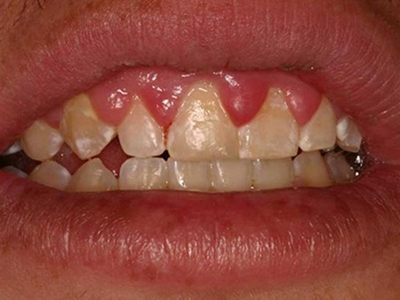

牙龈瘤是指发生在龈乳头部位的炎症反应性瘤样增生物,好发于女性,前磨牙区最为常见。牙龈瘤来源于牙周膜及牙龈的结缔组织,因其无肿瘤的生物学特征和结构,故非真性肿瘤,但切除后易复发,因此切除务必彻底,必要时拔除相关牙齿。

牙龈瘤多发于女性,以青年及中年人为常见,多发生于牙龈乳头部,位于唇、颊侧者较舌、腭侧者多,最常见的部位是前磨牙区。肿块较局限,呈圆形或椭圆形,有时呈分叶状,大小不一,直径由几毫米至数厘米。

肿块有的有蒂,如息肉状;有的无蒂,基底宽广,生长较慢,但在女性妊娠期间可能迅速增大。较大的肿块可以遮盖一部分牙及牙槽突,表面可见牙压痕,易被咬伤而发生溃疡,伴发感染。随着肿块的增长,牙槽骨壁逐渐被破坏,牙可能发生松动、移位。